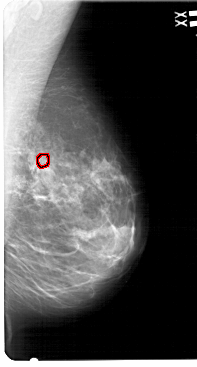

A_1546_1.LEFT_MLO

LEFT_MLO LINES 5491 PIXELS_PER_LINE 2986 BITS_PER_PIXEL 12 RESOLUTION 43.5 NON_OVERLAY

FILE: A_1546_1.RIGHT_MLO.OVERLAY

TOTAL_ABNORMALITIES 1

ABNORMALITY 1

LESION_TYPE CALCIFICATION TYPE PLEOMORPHIC DISTRIBUTION CLUSTERED

ASSESSMENT 4

SUBTLETY 1

PATHOLOGY BENIGN

TOTAL_OUTLINES 1

BOUNDARY